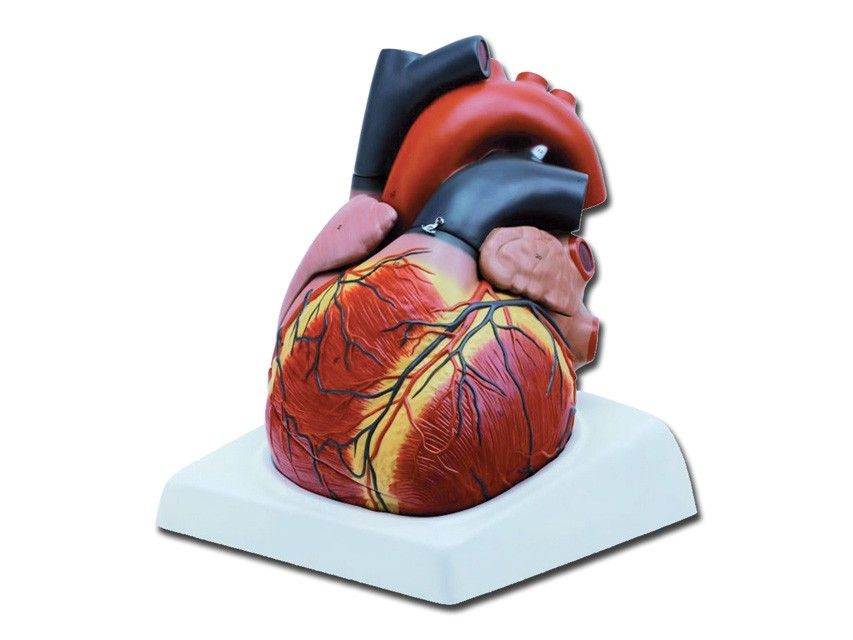

Modello Cuore - 4 Parti